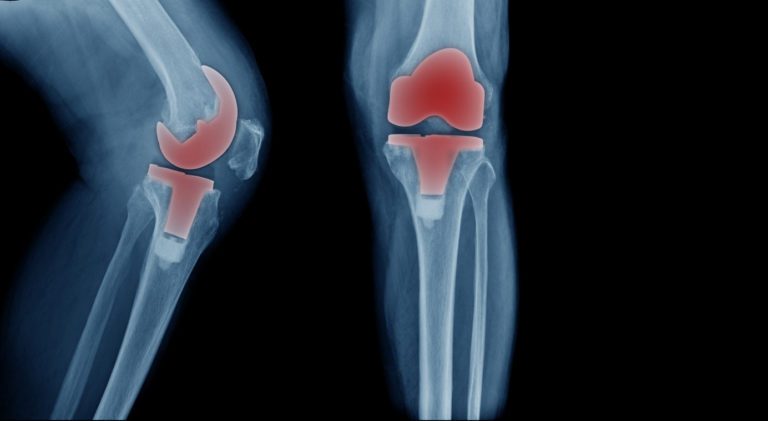

Partial Versus Total Knee Replacement

Your orthopedic surgeon will tell you if you need a partial or a total knee replacement, depending on the type, severity, and location of your joint damage. Whatever the case, you can receive one of today’s most innovative surgical interventions through knee replacement.

Other patients undergo total knee replacement, a more involved surgical procedure featuring:

- Full-width knee prosthesis

Experts at the Cleveland Clinic state that most knee replacement parts last about 15 years. Overall, patients express satisfaction with their new knees. They enjoy mobility and improved independence in accomplishing their daily tasks, working, and playing sports.